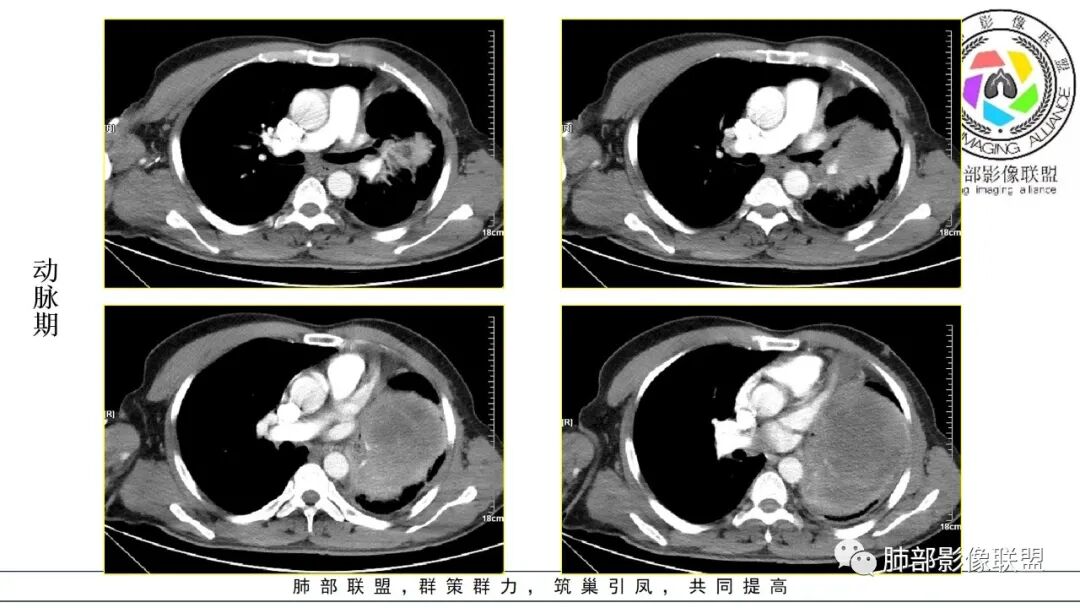

男,50岁,双下肢水肿10余天,发热3天。NSE、细胞角蛋白19片段增高。胸部CT:肺气肿背景,左下叶巨大肿块,边缘膨隆明显,与周围界限清楚,累及左肺门、左上叶,上叶支气管受压狭窄,下叶支气管截断,不均匀强化,湖泊样坏死,肿块边缘粗大点状钙化,肿块内血管影迂曲、模糊,蛇纹?考虑恶性,鳞癌?肉瘤样Ca?鉴别SFT。

2.左肺巨大块影,上部边界较清楚,占据胸腔大部,对于左肺,“占据”及“推移”兼而有之,左肺上叶支气管推移狭窄,下叶支气管截断。下肺动脉穿行!

3.病灶密度不均,轻度强化,坏死或液化范围甚大,边界可分辨,部分“壁”可见钙化。

4.病灶紧贴胸壁,胸壁未见栽赃侵入。

5.纵隔左移,左肺门变形。左肺门及纵隔未见明显增大淋巴结。